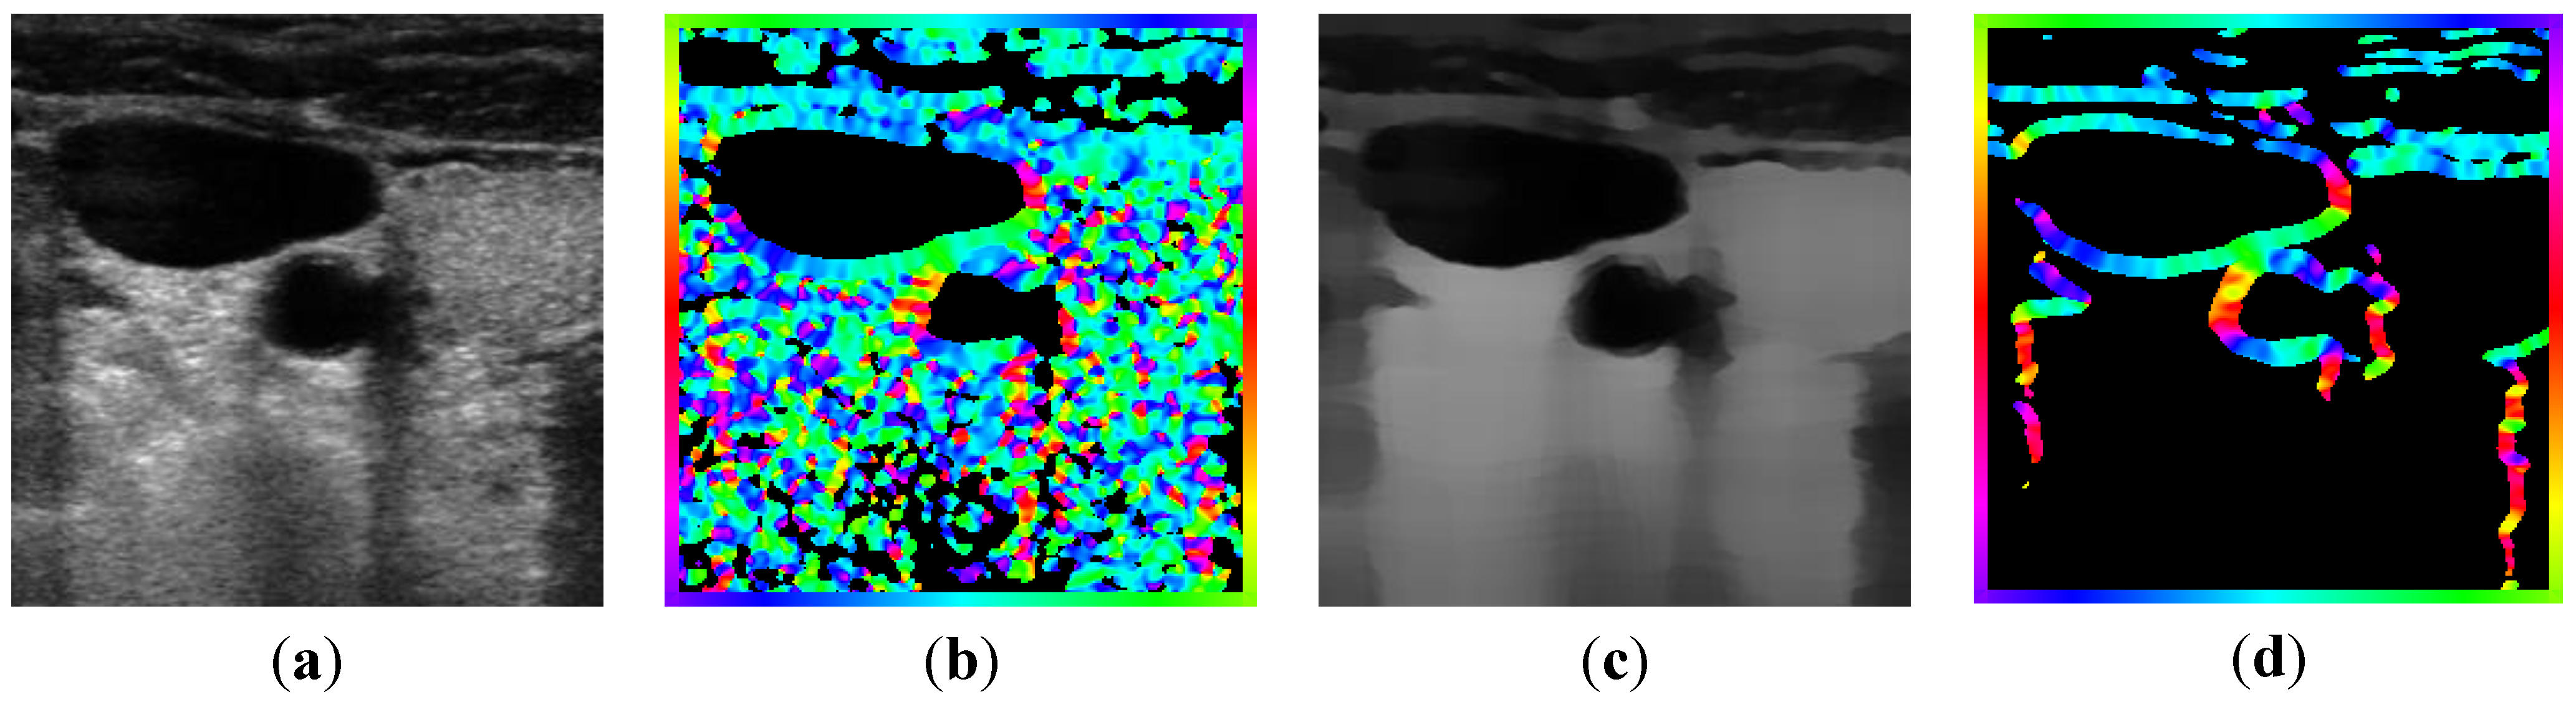

2.2.1. Feature Extraction

, and the magnitude projection image,

, and the magnitude projection image,  .

.

determinates the level of speckle noise, and therefore, it allows the control of the diffusion over time in Image (I).

determinates the level of speckle noise, and therefore, it allows the control of the diffusion over time in Image (I).

), and the pixel orientation, (

), and the pixel orientation, (  ), vector by means of function Av, which defines the angle between both vectors. The second objective function, f𝑔, Equation (22), aims to find shapes with a higher echogenicity given by the LIP-Sobel gra2-dient, Gv. To avoid the gradient generated by small variations in the intensity of the image, a threshold scheme is utilized. The function is set to the gradient if the threshold is higher than a defined value; otherwise, a penalization is applied to avoid the discontinuity in the shape of the ellipse and the gradient map. The third objective function, fb, Equation (23), acts in a similar way as the previous one, but in this case, a binary map, Bv, is used. Finally, the fourth objective function, fFRS, Equation (24), will guide the ellipse into the center of the artery using the FRS map. Once all the objective functions have been defined, the fitness function can be expressed as shown in Equation (25), where the weights, α1,α2,α3,α4, are incorporated for each respective objective function. After empirical tests, it was found that those values fixed to α1 = 100, α2 = 2, α3 = 100, α4 = 30 of the proposed method achieve satisfactory results.

), vector by means of function Av, which defines the angle between both vectors. The second objective function, f𝑔, Equation (22), aims to find shapes with a higher echogenicity given by the LIP-Sobel gra2-dient, Gv. To avoid the gradient generated by small variations in the intensity of the image, a threshold scheme is utilized. The function is set to the gradient if the threshold is higher than a defined value; otherwise, a penalization is applied to avoid the discontinuity in the shape of the ellipse and the gradient map. The third objective function, fb, Equation (23), acts in a similar way as the previous one, but in this case, a binary map, Bv, is used. Finally, the fourth objective function, fFRS, Equation (24), will guide the ellipse into the center of the artery using the FRS map. Once all the objective functions have been defined, the fitness function can be expressed as shown in Equation (25), where the weights, α1,α2,α3,α4, are incorporated for each respective objective function. After empirical tests, it was found that those values fixed to α1 = 100, α2 = 2, α3 = 100, α4 = 30 of the proposed method achieve satisfactory results.